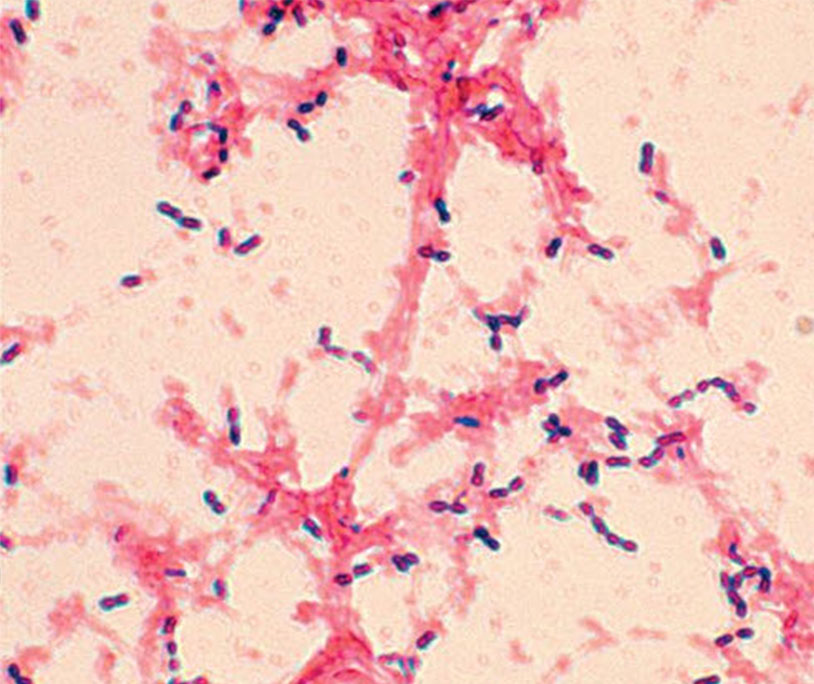

Your Gram stain is complete and correct. Which of the following statements would apply to the image you see?

unknown is negative, as S.aureus is known positive, so it can be ruled out

Your Gram stain is complete and correct. Which of the following would apply to the image you see?